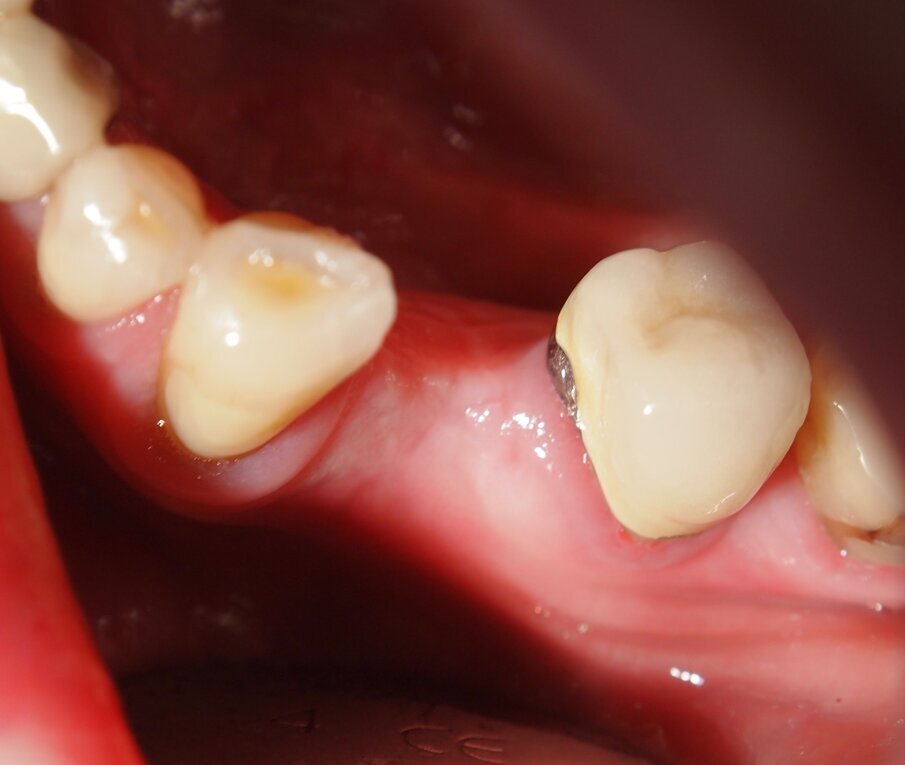

Fig. 3 - Caso clinico 1. Incisione dei tessuti molli con laser a diodi da 915 nm ed inserto in zaffiro. Si osservi l’annerimento della porzione terminale dell’inserto, ad indicarne l’avvenuta attivazione.

Fig. 4 - Caso clinico 1. Incisione dei tessuti molli con laser a diodi da 915 nm e inserto in zaffiro. L’inserto viene condotto lentamente con un movimento simile a quello della lama fredda.

Fig. 5 - Caso clinico 1. Incisione dei tessuti molli con laser a diodi da 915 nm e inserto in zaffiro. Si apprezza macroscopicamente l’assenza di fenomeni di carbonizzazione.